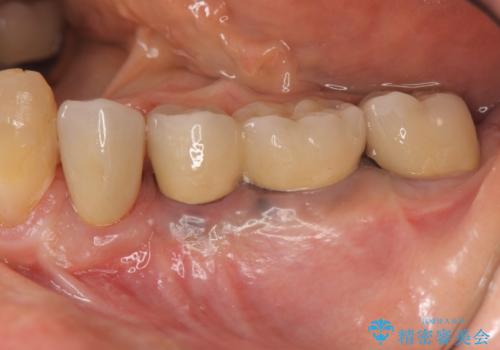

[遊離歯肉移植] インプラント周囲の角化歯肉の獲得

![[遊離歯肉移植] インプラント周囲の角化歯肉の獲得の症例 治療後](https://seimitsushinbi.jp/wp/wp-content/uploads/2020/01/f8e73ac6cf91eb450f830ba6ff08cd3a-500x350.jpg?v=1580303890)